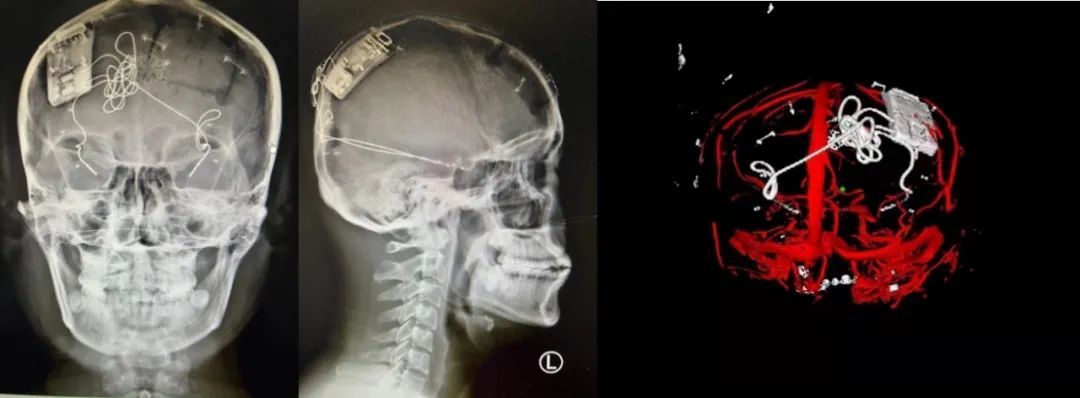

本次手術(shù)過程順利,術(shù)中刺激器各項(xiàng)指標(biāo)均工作正常,術(shù)后重建顯示電極位置精準(zhǔn),腦電信號(hào)清晰?;颊邽槟行裕朐汉笤\斷為雙側(cè)顳葉癲癇,此類癲癇為開顱手術(shù)的相對(duì)禁忌癥,在藥物無法控制的情況下,傳統(tǒng)治療效果欠佳 。

團(tuán)隊(duì)根據(jù)術(shù)前計(jì)劃,在手術(shù)機(jī)器人輔助下完成雙海馬長軸電極及 IPG 植入,術(shù)后重建顯示電極位置精準(zhǔn),腦電信號(hào)清晰。術(shù)后第二天,患者即下床活動(dòng),身體狀況恢復(fù)良好。